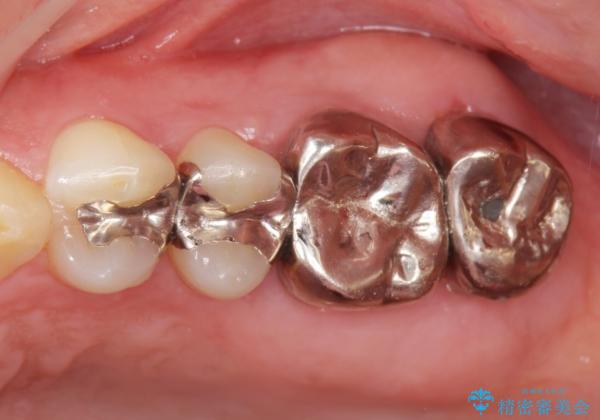

- 銀歯をやりかえたいが他院で抜歯と言われセカンドオピニオンで来院。適合の悪い被せ物が入っており、まずは古い材料、虫歯をとり保存可能か確かめる必要があり、拡大鏡下で全て取り除いたら歯質が歯茎の中まで虫歯がありました。このまま無理やり型取りをして被せ物を作っても不適合な被せ物が入る可能性が高いため歯茎を切り取る手術(ディスタルウェッジ)を行いました。そして再根管治療を行いゴールドの被せ物で治療を行いました。

- PGAクラウン・仮歯 13.2万円×2 精密根管治療(リトリートメント)・コア 16.5万円×2 ディスタルウェッジ 1万円費用は治療当時の料金となります